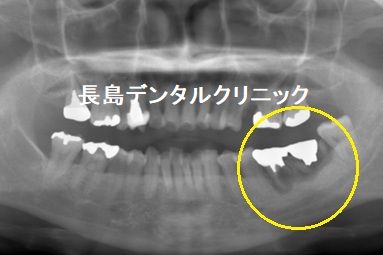

1、インプラント埋入前

今回の症例では左下奥歯2本が保存できず、インプラントを希望しま

したが、骨がなくインプラントが埋入できないので事前に骨を作るこ

とが必要と診断された症例です。レントゲン画像の黄色い丸印の2本

の歯が保存できない状態です。かなり炎症が進んでいます。下の奥歯